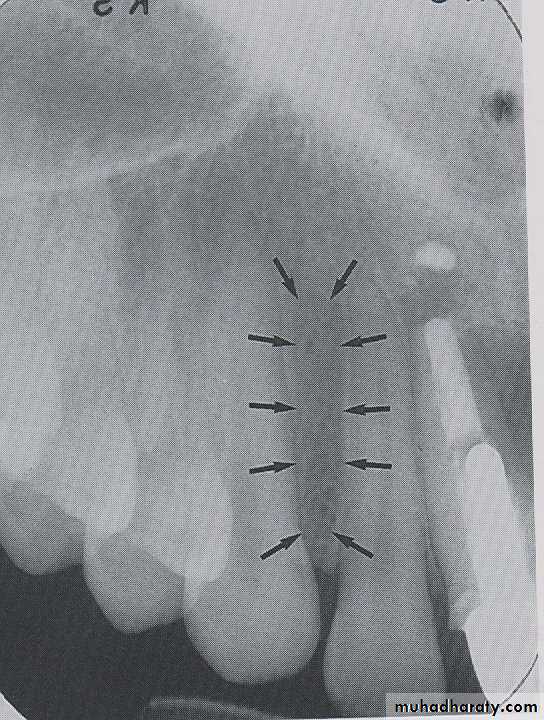

NUTRIENT CANALS

:

Nutrient canals carry a neurovascular bundle and appear as radiolucent lines of fairly uniform width. They are most often seen on mandibular periapical radiographs running vertically from the inferior dental canal directly to the apex of a tooth or into the inter dental space between the mandibular incisors.